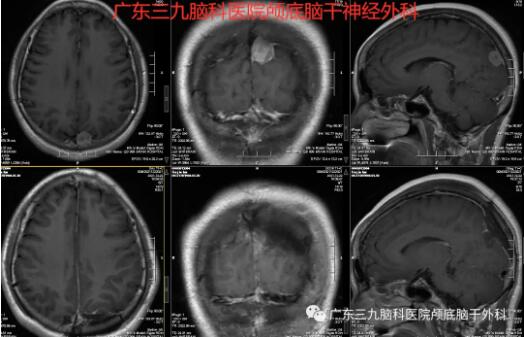

经检查发现:MR示左侧枕顶部上矢状窦旁示一大小约16×15×18mm的结节状不均等T1等、短T2异常信号影,FLAIR序列呈等、低信号影,DWI呈等、稍低或稍高信号,ADC图呈等信号影,增强扫描后呈明显强化,邻近脑膜可见强化;双侧大脑半球皮层下白质内及双侧半卵圆中心、放射冠示散在斑点状等T1长T2异常信号影,FLAIR序列呈高信号。CTA示左侧枕顶部镰旁团块状占位性病变内存在多发小血管,病变紧贴上矢状窦。双侧颈内动脉C1段各示一囊状突起影,大小分别约为右侧6.7×4.1mm、左侧6.4×3.8mm,前交通动脉略显局部隆起。

术前MR

术前术后MR对比